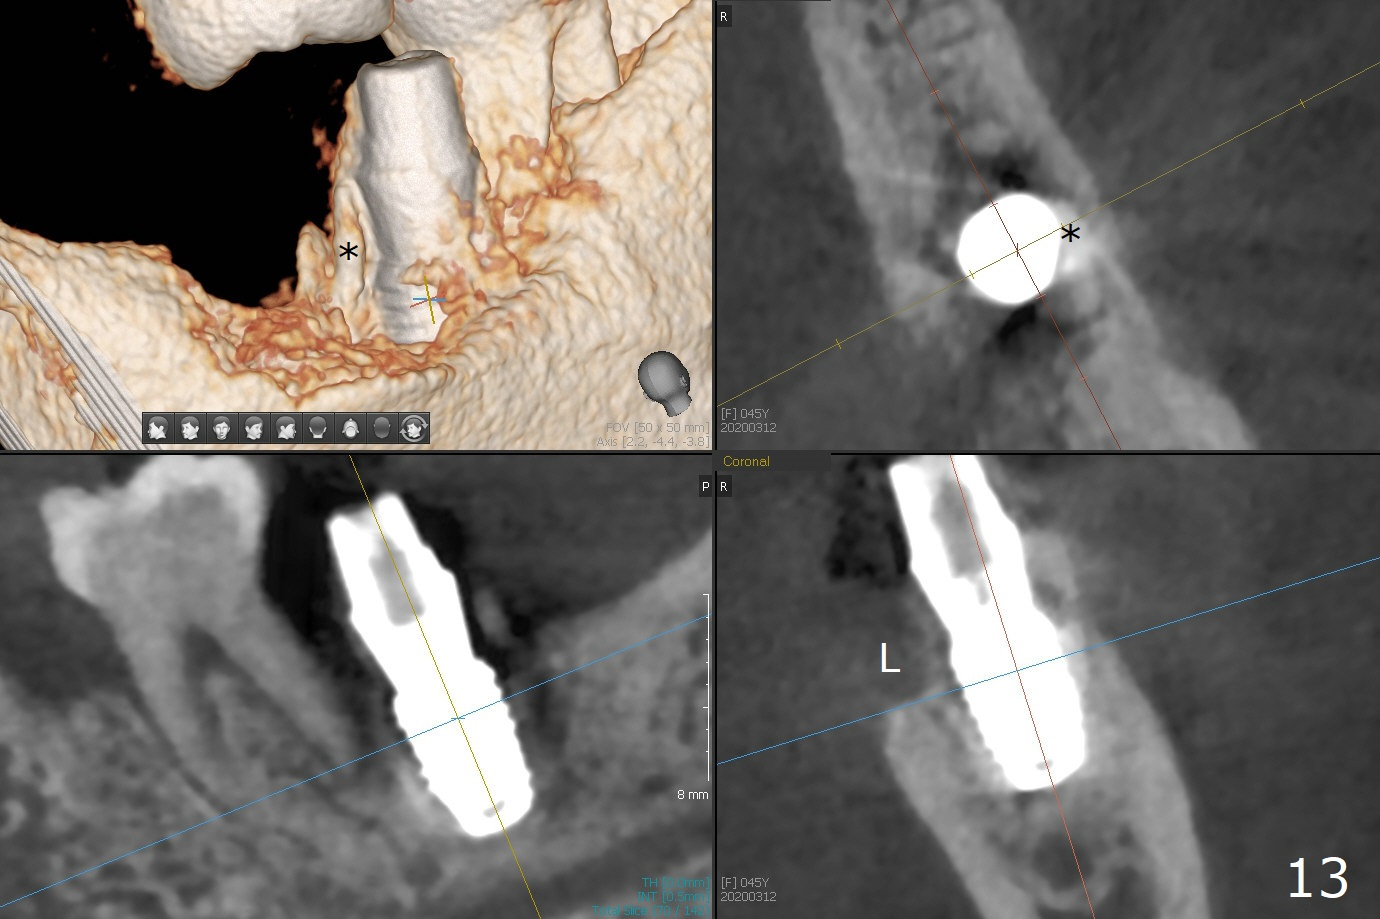

Socket shield (partial extraction therapies) is going to be conducted in this case to form a substitute buccal plate of the 2nd molar (Fig.1 *). The apex of the shield that contacts the 4.5x10 mm dummy implant cannot be removed because of poor access (Fig.2 * (12 mm offset)). Due to high bone density, a 4.5 mm drill has to be used in order to place a 5x7.3 mm definitive implant (Fig.3). In spite of the fact that the implant seems to be completely seated, the implant is ~ 1 mm supracrestal lingually. After implant removal, a 4.5x11.5 mm drill cannot reach the depth due to high bone density. 800 RPM instead of 50 RPM may help. When the implant is reseated, it appears to be .5 mm deeper than before clinically, although it looks incompletely seated in X-ray (Fig.4 <). The insertion torque is 60 Ncm. Allograft mixed with PRF is placed around the implant with cover screw, particularly mesiolinguodistal (Fig.4 *). The sockets of #17 and 18 are approximated with the help of 2 piece of PRF and collagen plug. The wound dehisces 9 days postop (Fig.5,6), although asymptomatic. Forced closure of the sockets with suture seems unnatural. An immediate provisional should have been fabricated. CT shows possible loss of part of bone graft (Fig.7). Regraft seems necessary in the appointment of uncover. Antibiotic is prescribed for another week. The gingiva seems healthy around the exposed healing screw 16 days postop (Fig.8). After debridement, the healing screw is then changed to a 4.5x5 mm healing abutment. The majority of the bone graft is lost without immediate provisional in 4 months (Fig.9 * (<: socket shield)). Then a 5.5x5 mm healing abutment is inserted for impression next appointment. A 5.2x4.5(4) mm cemented abutment is placed before impression (Fig.10). With socket shield (Fig.11 ^), the buccal gingiva looks more keratinized than the lingual one (Fig.12 *). Photos are taken immediately pre-cementation. Socket shield (*) covers the implant and abutment buccally (Fig.13 CT taken immediately pre-cementation).